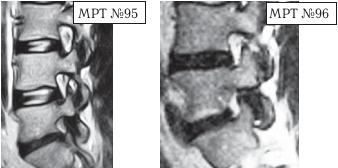

Иллюстрация к книге — Остеохондроз для профессионального пациента [i_114.jpg]

На МРТ № 94 наблюдается позвоночно-двигательный сегмент в стадии развития дегенерации. Высота межпозвонкового диска ещё сохранена, однако уже наблюдается разрушение пульпозного ядра, нарушение гидратации и так далее. В общем, явные признаки развития дегенеративно-дистрофического процесса. Конгруэнтность дугоотростчатого сустава пока ещё не нарушена, суставная капсула визуально целая, но с явными признаками травматизации за счёт перерастяжения. Несмотря на такую травматизацию, вследствие нестабильности, выраженную дегенерацию, человек не чувствует боли из-за работы вышеупомянутых рецепторов в дугоотростчатом суставе, благодаря сигналам которых запускается механизм выработки эндогенных опиатных пептидов. То есть, получается своеобразный феномен: наблюдается постоянная травматизация, а боли человек не чувствует.

Однако когда, к примеру, речь идёт не только о травматизации дугоотростчатого сустава за счёт перерастяжения суставной капсулы, а о стенозе фораминальных отверстий с ущемлением спинномозгового корешка, то здесь уже пациент чувствует явную боль, поскольку организм не справляется с данной ситуацией. Своей «болью», в качестве сигнала «тревоги», он «даёт знать» человеку о наличии серьёзной проблемы.